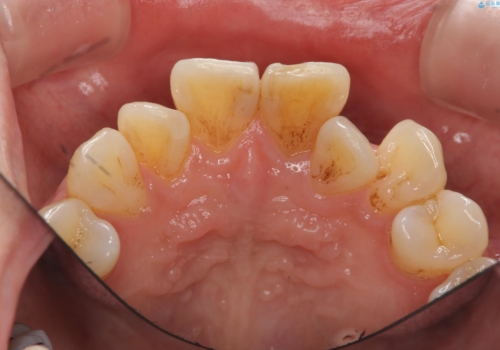

歯の変色 前歯の審美改善

- 前歯の変色の改善を求めて来院されました。

X線写真より、以前に神経の治療が為され変色をきたしている状態であることがわかりました。

根管内の感染は認められないのでセワミッククラウンの製作・装着を行い審美性を改善します。